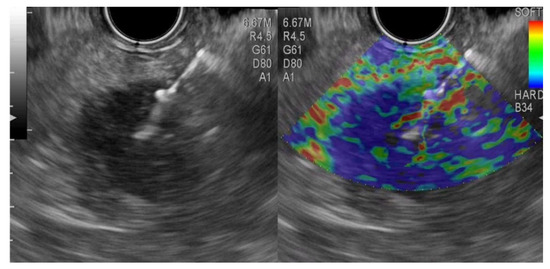

2.4. Procedures